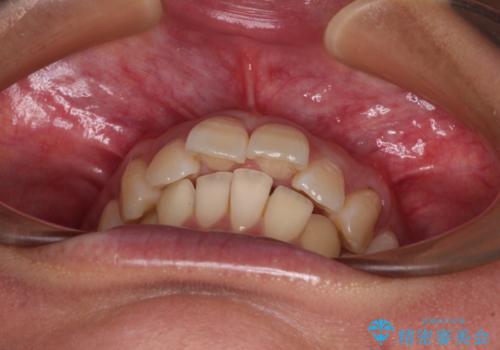

- 上顎前歯の突出感を気にして来院された患者様です。

舌の突出癖の影響で、歯列が前方に飛び出いた形態となっている状態でした。

抜歯矯正とするような歯列ではないため、舌のトレーニングを行いながら歯列を側方に拡大させることで口元の突出感を改善することとしました。